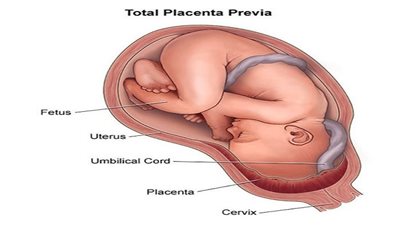

ولمن ترغب في معرفة إجابة سؤال ما هو التجمع الدموي تحت المشيمية؟، فحسبما جاء بموقع" كليفلاند" الطبي، التجمع الدموي تحت المشيمة عبارة عن تراكم الدم بين جدار الرحم والغشاء الخارجي للمشيمة، والذي يعرف بالغشاء المشيمي، ويعمل هذا الغشاء كحلقة وصل بين المشيمة وجدار الرحم، ويفصل الكيس الأمنيوسي الذي يحيط بالجنين عن باقي الرحم.

ويحدث هذا التجمع؛ نتيجة نزيف صغير داخل الرحم، ويُعد أحد الأسباب الأكثر شيوعًا للنزيف المهبلي خلال الثلث الأول أو الثاني من الحمل، خاصة بين الأسبوعين الـ 10 و20.